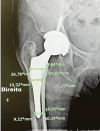

Objective This study aims to compare the proximal femoral bone density changes in follow-up X-ray imaging and the proximal filling ratios of stems between anatomical and double-tapered wedge stem designs. Methods Patients aged between 18 and 80 years who received primary total hip arthroplasty using both types of stems between 2017 and 2019 and had follow-up tests for up to a year were included in the study. Canal filling ratios at 3 levels (lesser trochanter [LT], 2 cm above LT, and 7 cm below LT) using the optimal densitometry method. Femoral bone density changes were measured using the Gruen zoning method. Results A total of 92 patients (76% female and 24% male) met the inclusion criteria for this study. The mean age was 53.86 ± 13.00 years. The canal filling ratio in the double-tapered wedge group (Accolade II) was significantly higher than that in the anatomical stem group (ABGII) ( p < 0.001, p < 0.001, and p = 0.013) for all levels of measurement. No significant difference was observed between both types of stems in femoral bone density changes in zones 1 and 4. However, there were significant differences in femoral bone change, with bone loss being higher in the anatomical stem group in zone 7 (-25% versus -17%; p = 0.010). Conclusion Double-tapered wedge stem had a significantly higher canal filling ratio than the anatomical stem at all levels but had less femoral bone density loss in the follow-up postoperative imaging in zone 7. Furthermore, in zones 1 and 4, there was no significant difference in femoral bone density loss.

Figures